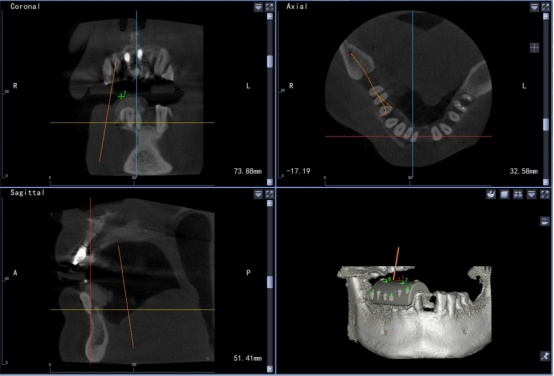

高精准度:采用国际领先的红外光学定位技术,准确为医生指引方向,准度可达到0.3mm,种植体植入方向、位置、角度、深度一目了然,确保了种植手术的可预期性,显著提高种植精度。

成功率高:术前口内模拟种植,避开神经血管,设计种植方案,运用计算机三维重建与可视化技术,清晰展现患者口内结构,保证了复杂病例的成功率。

实时引导:全程监控手术工具与解剖结构的位置关系,轻松把控种植位点、角度和深度,实时引导术者按计划进行种植。

数字化动态导航系统犹如口腔中的GPS导航”,简单来说就是通过虚拟数字化软件设计,提前设计好修复体三维位置,结合精准的红外光学定位技术,在种植手术过程中,实现全程实时的导航。使使种植医生实时监控和调整手术的进程。